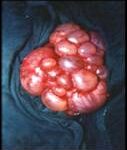

Your child will need this operation because a kidney is not working properly. This could cause infections which may damage the other kidney, and makes it more likely that your child will have high blood pressure at some point in their life. Being left with one kidney should not cause your child any problems.

The surgeon will remove your child’s damaged kidney through a cut (incision) in his or her side. The operation takes between one to one-and-a-half hours.